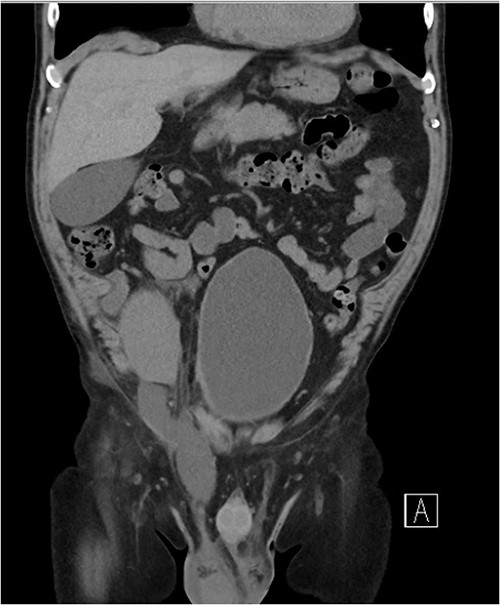

Five days later, the patient had another ultrasound and an ensuing CT KUB given recurrence of a painful groin swelling overnight. It showed a reaccumulation of the pelvic fluid collection, which extended into the groin toward the scrotum with two pockets of fluid collection measuring 4.6 × 6.5 × 2.7 cm (42 ml) and 7.7 × 3.5 × 4.6 cm (66 ml) (Figs 2 and 3). We temporized the situation by aspirating 35 ml of fluid by the bedside under ultrasound guidance for symptom relief and booked him for an elective operation given the complex anatomy of the collection.

(A, B) Targeted ultrasound showing reaccumulation of a peri-transplant collection which appeared multiloculated measuring a total of 100 ml extending into the right groin.

Coronal CT scan showing lobulated low-density fluid collection adjacent to the lower pole of the transplant kidney in the right iliac fossa and extending into the superficial inguinal canal tracking along the inguinal and scrotal hernia with a maximal width of 43 mm in transverse diameter.